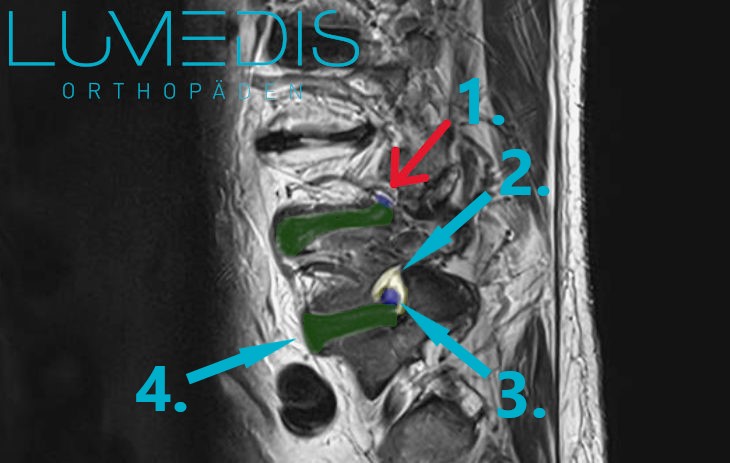

MRT der LWS (seitlich, T2) mit einem Bandscheibenvorfall L5/S1:

MRT der Brustwirbelsäule T2 Wichtung

Legende: Wirbelkörperbruch der Brustwirbelsäule

Grün: gesunde Wirbelkörper

Rot: gebrochener Wirbelkörper (komplexe Deckplattenimpressionsfraktur 12. Brustwirbel)

Blau: Bandscheiben